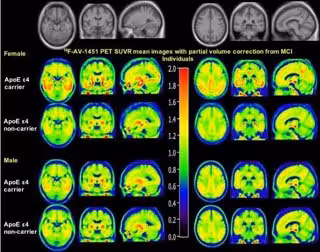

Imagen de PET de cómo el sexo modula el efecto de ApoE e4

Imagen de PET de cómo el sexo modula el efecto de ApoE e4 - PARANJPE M, LIU M, PARANJPE I, ET AL.

Este es el primer trabajo que demuestra que el sexo modula el efecto de ApoE e4 sobre el depósito de tau cerebral, medido usando imágenes 18F-AV-1451-PET, en la corteza entorrinal, la amígdala, el giroscopio parahipocampal y el cingulado posterior de los cerebros de pacientes con deterioro cognitivo leve (DCL). Sorprendentemente, las mujeres experimentan un mayor aumento en la deposición de tau cerebral en estas regiones en comparación con sus contrapartes masculinas.